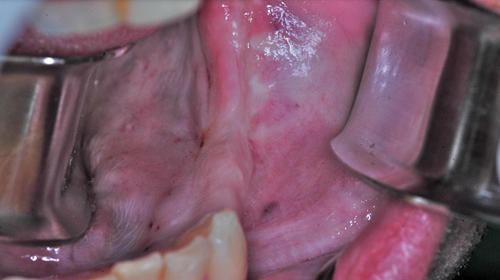

Palabras Clave: ELG: Estereolitográfico OH: Oclusión Habitual ORC: Oclusión en Relación Céntrica Paciente de 35 años de edad ,sexo masculino que lo derivan para implantar el tercer cuadrante. A la auscultación presenta ruidos articulares de tipo chasquido que remiten temporalmente luego de limitación de apertura bucal y maniobras quinesiológicas distractoras. También se observan recidivas de caries en algunos empastes y falta de disclusión canina de ambos lados. Se estudia el caso desde un punto de vista clínico, scanografico mediante Dentascan y tridimensional mediante montaje en articulador. A partir del scanner se obtienen datos para confeccionar modelo estereolitográfico (ELG),operar en el y construir férula quirúrgica dento-muco soportada. Habitualmente se procede directamente a implantar, dado que ese era el requerimiento del profesional derivante y el deseo del enfermo. Sin embargo, esa actitud enmascararía otro tipo de problemas que la boca presenta. Se consulta al odontólogo derivante, y coincide con mi opinión acerca de que si solo se lo implanta, sin corregir la posición mandibular, la situación de las ATMs, los empastes sin anatomía y la falta de disclusiones, el resultado final no será el deseado y su eficacia masticatoria no funcionará optimamente. Consultado el paciente coincide y acepta ese concepto y entonces procedemos a confeccionar un Jig de Lucia a partir del montaje de estudio, y lo dejamos puesto en boca toda la noche anterior a la consulta, para proceder a realizar un ajuste oclusal al día siguiente sin engramas anteriores, lo que facilita no tener que relajar nuevamente con laminillas de Long. En esta etapa pierde el implante correspondiente a la pieza 4.7 que traía en boca. Estabilizado el sistema, procedemos a la parte quirúrgica, comenzando por instalar la férula, retirar opérculos gingivales mediante bisturí circular, fresado óseo e instalación de implantes ,toma de impresión a cubeta fenestrada (pegando con metacrilato sin cambios dimensionales, los transfers a la cubeta especialmente diseñada.(1º método de pasividad protética utilizado), e instalación de tornillos de cicatrización. Inmediatamente de retirada la cubeta de boca y colocadas las réplicas de los implantes, procedemos a ferulizar los “ápices” de las réplicas para que no sufran movimientos durante el llenado de la impresión.(2º método de pasividad protética utilizado). Controlamos radiograficamente Tres meses después, procedemos a tomar nuevos registros de arco facial, registros intermaxilares en Oclusión en Relación céntrica, montaje de los modelos obtenidos intra operatoriamente y confección de un conjunto de cuatro coronas provisionales de metacrilato en el sector implantado y las correspondientes al maxilar superior. Verificada la perfecta función de todos los componentes, ausencia de todo tipo de síntoma y comprobada la paz en todo el sistema, procedemos tiempo después a confeccionar las fundas definitivas, que constituyen el “cerrojo” de la dinámica del mismo. Por último, corroboramos la oclusión fundamentalmente en lo que hace a la:

Se observan depósitos de sarro incluso en oclusal

La anatomía de las piezas protéticas no responden a la función